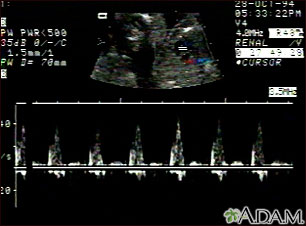

This is an ultrasound showing a ventricular septal defect pattern of the fetal heartbeat. Some ultrasound machines have the ability to focus on different areas of the heart and evaluate the heartbeat. This is useful in the early diagnosis of congenital heart abnormalities.